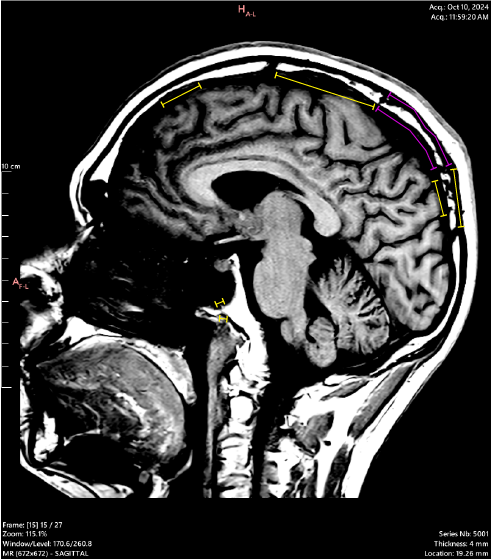

OCT 2024:

These are corresponding slices from 2 MRI series performed in OCT 2024 (left) and JULY 2025 (right). They show progressive, pathological boney change and osteolysis (bone destruction) over the 9 months between imaging. The yellow (OCT) and green (JULY) lines highlight visible and active bone destruction.

The pink is a significant region of interest as it shows not only the destruction of bone, but a “caving-in” change in the bone shape; Interestingly, this change is physically visible on the scalp as depicted below.

Same area shown in the above MRIs; there is no tangible bone when pressing on it, and it elicits an immensely uncomfortable feeling, as well as sensory sensations in other areas of the head.

There are multiple “soft spots” like this across my head - some are more easily visible in photographs, though all can be pressed like such to a similar but varying physical/sensory response.